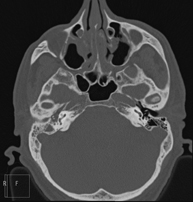

- TC Oídos Prueba radiológica que consiste en obtener imágenes del oído de alta definición anatómica (conducto auditivo interno y externo, tímpano, huesecillos del oído), mediante el empleo de un equipo de TC (Tomografía Computarizada). Indicaciones: trastornos de la audición, cuadros vertiginosos, mareos, acúfenos (pitidos). Prueba radiológica que consiste en obtener imágenes del oído de alta definición anatómica (conducto auditivo interno y externo, tímpano, huesecillos del oído), mediante el empleo de un equipo de TC (Tomografía Computarizada). Indicaciones: trastornos de la audición, cuadros vertiginosos, mareos, acúfenos (pitidos).

- TC Senos paranasales Prueba radiológica que consiste en obtener imágenes de los senos paranasales de alta definición anatómica, mediante el empleo de un equipo de TC (Tomografía Computarizada). Indicaciones: cefalea, tos crónica, mucosidad, infecciones faciales. Prueba radiológica que consiste en obtener imágenes de los senos paranasales de alta definición anatómica, mediante el empleo de un equipo de TC (Tomografía Computarizada). Indicaciones: cefalea, tos crónica, mucosidad, infecciones faciales.

- TC Peñascos Prueba radiológica que consiste en obtener imágenes del hueso peñasco del temporal (oído interno, medio y externo) de alta definición anatómica mediante el empleo de un equipo de TC (Tomografía Computarizada). Indicaciones: pérdida de audición súbita o crónica, cuadros vertiginosos, mareo, malformaciones congénitas. Prueba radiológica que consiste en obtener imágenes del hueso peñasco del temporal (oído interno, medio y externo) de alta definición anatómica mediante el empleo de un equipo de TC (Tomografía Computarizada). Indicaciones: pérdida de audición súbita o crónica, cuadros vertiginosos, mareo, malformaciones congénitas.